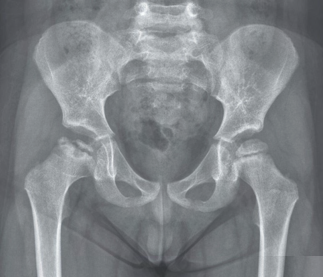

Recent studies indicate that Generative Pre-trained Transformer 4 with Vision (GPT-4V) outperforms human physicians in medical challenge tasks. However, these evaluations primarily focused on the accuracy of multi-choice questions alone. Our study extends the current scope by conducting a comprehensive analysis of GPT-4V's rationales of image comprehension, recall of medical knowledge, and step-by-step multimodal reasoning when solving New England Journal of Medicine (NEJM) Image Challenges - an imaging quiz designed to test the knowledge and diagnostic capabilities of medical professionals. Evaluation results confirmed that GPT-4V outperforms human physicians regarding multi-choice accuracy (88.0% vs. 77.0%, p=0.034). GPT-4V also performs well in cases where physicians incorrectly answer, with over 80% accuracy. However, we discovered that GPT-4V frequently presents flawed rationales in cases where it makes the correct final choices (27.3%), most prominent in image comprehension (21.6%). Regardless of GPT-4V's high accuracy in multi-choice questions, our findings emphasize the necessity for further in-depth evaluations of its rationales before integrating such models into clinical workflows.